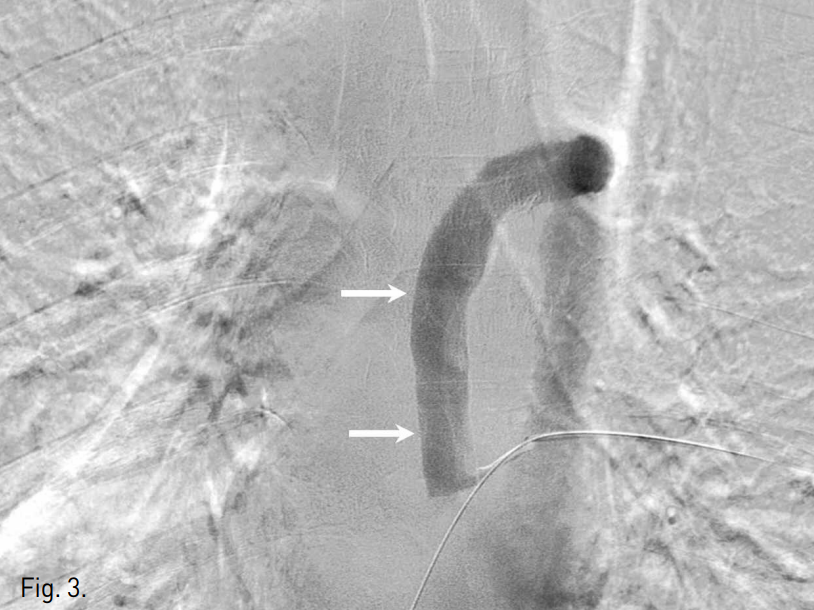

양측 상지정맥 천자 후 시행한 중심정맥조영술 사진에서 양측 쇄골하정맥부터 양측 중심정맥의 완전 폐색이 관찰되었으며, 우측 상지의 혈류가 우측 외흉정맥(lateral thoracic vein), 늑간정맥, 기정맥 (azygos vein)을 순차적으로 통해 심장으로 유입되고 있었음 (Fig. 1).

Fig. 1

Both central venograms obtained with injection of contrast medium via both arm veins (A: left, B: right) show complete obstruction of right distal and left proximal subclavian veins with non-visualization of more central veins. The venous blood flow from right upper extremity drains into the heart via collaterals of right lateral thoracic (arrows), intercostal, azygos veins.